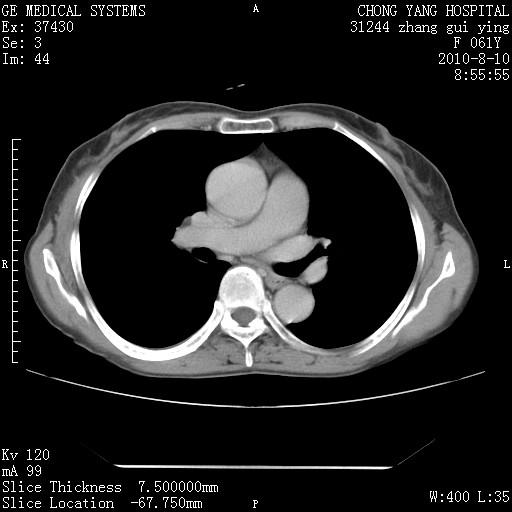

标题: CT28314:F61Y胸部增强,发热咳嗽一周入院,后面的为一周前平 [打印本页]

标题: CT28314:F61Y胸部增强,发热咳嗽一周入院,后面的为一周前平

1、支持考虑右侧中央型肺癌伴右肺中叶节段性不张及下叶支气管黏液痰栓    2、左肺上叶舌段感染。

支持3楼意见,还要考虑:纵隔及肺门淋巴结转移、右侧少量胸腔积液。

确切的说:1:右肺下叶中心型肺癌侵及中叶支气管并中叶不张,纵膈淋巴结转移。2:左肺舌叶炎症。3:右侧胸腔少量积液

块影平扫32hu,动静脉期62-70hu.

1:右肺下叶中心型肺癌侵及中叶支气管并中叶不张,纵膈淋巴结转移。2:左肺舌叶炎症。3:右侧胸腔少量积液。支持!

右肺下叶中心型肺癌侵及中叶支气管并中叶不张,纵膈淋巴结转移。2:左肺舌叶炎症。3:右侧胸腔少量积液